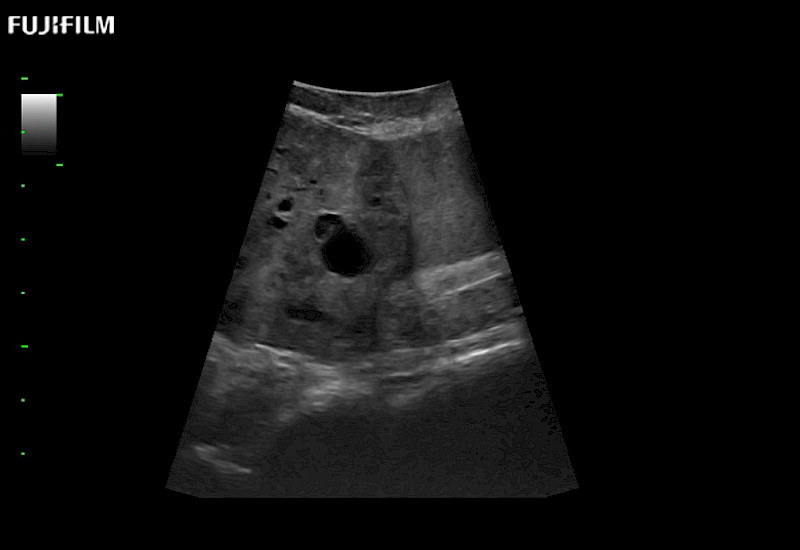

The ARIETTA 750 incorporates all of the proven technologies and functions that medical professionals have come to expect from Fujifilm Healthcare.

ARIETTA 750 is the definitive diagnostic ultrasound solution for any clinical setting - Private Office, Imaging Center, or Hospital. The ARIETTA platform provides the ultimate in clinical performance with its state-of-the-art features and large user-friendly display.

The ARIETTA 650 DI combines trusted Fujifilm Healthcare technologies and features tailored for surgical oncology.

Designed to meet the demands of surgeons, the ARIETTA 650 DI offers precise guidance. Its advanced capabilities and large, intuitive display offer accurate and efficient care in operating rooms and specialized surgical settings.